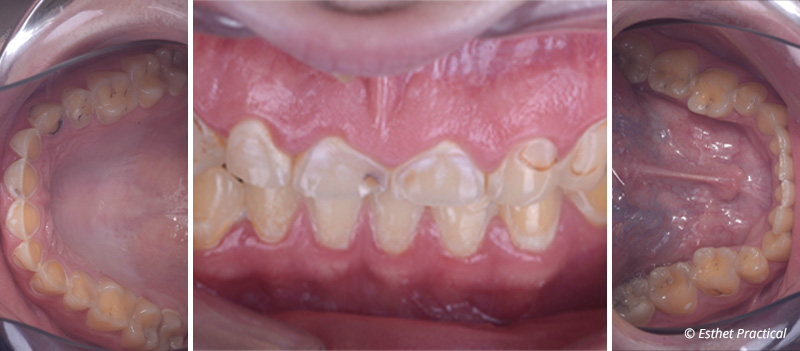

Fig. 01 : situation initiale.

Ce jeune patient consulte pour l’aspect usé de ses dents.

Il se plaint par ailleurs de reflux gastro-œsophagiens, pense serrer les dents et ressent des contractures des mâchoires au réveil. L’étiologie érosive et attritive de l’usure semble donc évidente dans cette situation. L’observation du visage montre des lèvres pincées et un sourire récessif.

Le plan de traitement va consister à surélever la dimension verticale dans le but de créer un espace disponible à la réalisation de restaurations en céramique collées tout en préservant au maximum l’émail résiduel.